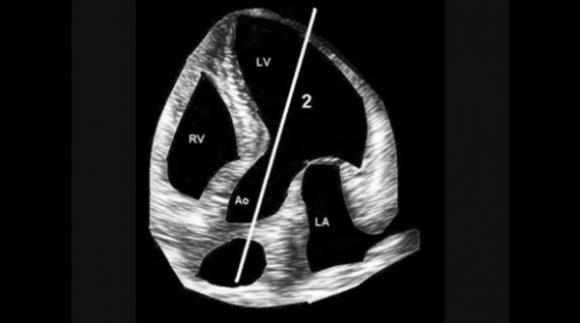

El Dr. Mario Jorge Mc Loughlin y el Dr. Santiago Mc Loughlin lo llevaron a cabo en forma experimental en centros privados en los que trabajo, ya que para desarrollarlo fue necesario tener aparatos de ecocardiografía para correlacionar lo auscultado con los resultados. Pero el objetivo es un aparato no más grande que un teléfono celular para auscultar a los pacientes en el consultorio médico o “bed-side”.